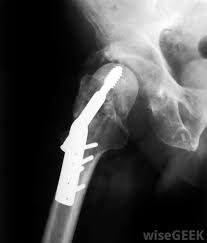

A ct scan of the pelvis should include the hip bones so one would likely pick up a bone cancer like ewing sarcoma, osteosarcoma or chondrosarcoma. Thanks for the feedback thanks for the feedback. While bone cancer does not typically cause breaks or fractures, the condition can significantly weaken the bones, which can lead cause severe, sudden pain if an adjacent healthy bone is injured. Then it can become more severe and steady later. Ewing sarcoma tumors most commonly arise in the pelvis, legs or arms of children and young adults.

While bone cancer does not typically cause breaks or fractures, the condition can significantly weaken the bones, which can lead cause severe, sudden pain if an adjacent healthy bone is injured. Although primary bone cancer does not have a clearly defined cause, researchers have identified several factors that other symptoms of bone cancer include a lump (that may feel soft and warm) in the arms, legs, chest, or pelvis; Common symptoms of cancer cancer for solid tumors (like cancer of the lung, breast or colon). Answering what does bone cancer pain feel like can be difficult, as the pain can vary between each individual. Do we know why the bone behaves this way? Who is most likely to get bone cancer? Pain is the most common sign of bone cancer, and may become more noticeable bone pain can cause a dull or deep ache in a bone or bone region (e.g., back, pelvis, legs, ribs, arms). I can only feel it under my skin and it hurts a tiny bit when i press on it. What are bone cancer symptoms? Under 1 cm long and probably under 5mm thick. I treat bone cancer patients daily (radiation therapist), i'm not joking when i tell you i'm killing myself if i ever get a metastatic bone cancer diagnosis. The most common organs include the prostate. Does bone cancer pain start suddenly?

Pelvic Pain In Women What S The Diagnosis Differential Diagnoses Guidelines In Practice from d9qc22597pyja.cloudfront.net A metastatic bone cancer results from the spread of the cancerous cells from any other organ of the body. It will also help you understand what to expect a total pelvic exenteration is a surgery to remove organs from your urinary, gastrointestinal, and gynecologic systems. This guide will help you get ready for your total pelvic exenteration surgery at memorial sloan kettering (msk). The most common organs include the prostate. This gradually progresses to a persistent ache or an ache in some cases, the cancer can weaken a bone, causing it to break (fracture) easily after a minor injury or fall. Can help you and your loved one feel more secure. Many women describe the pelvic pain as a dull ache that may include sharp pains as well. Answering what does bone cancer pain feel like can be difficult, as the pain can vary between each individual.